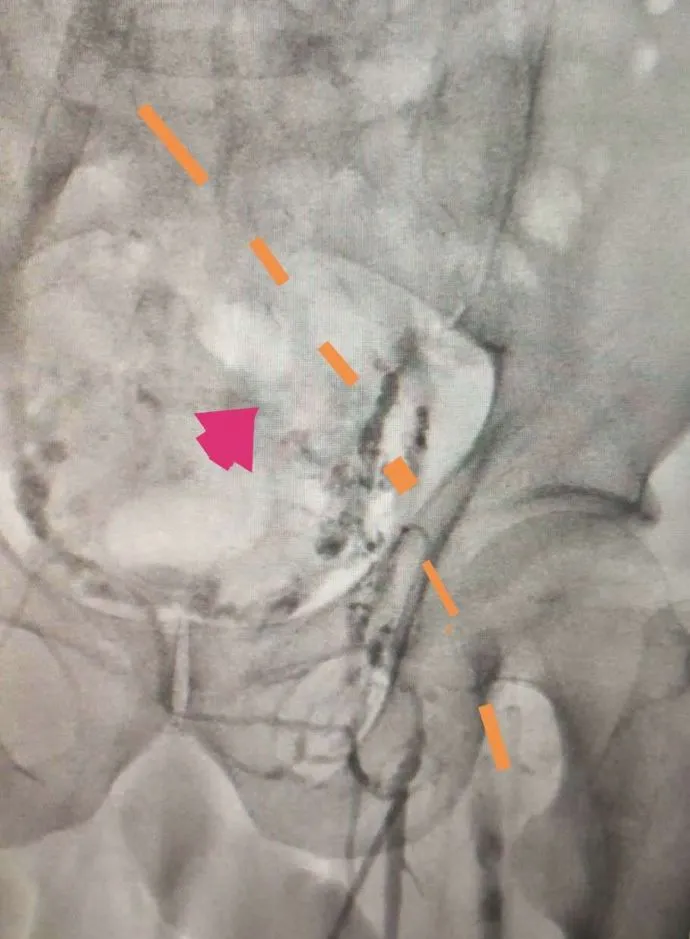

通过下图DSA造影可以看到,治疗前,血管几乎被完全堵塞;治疗后,血管通畅。

治疗前

治疗后

(治疗前后对比)